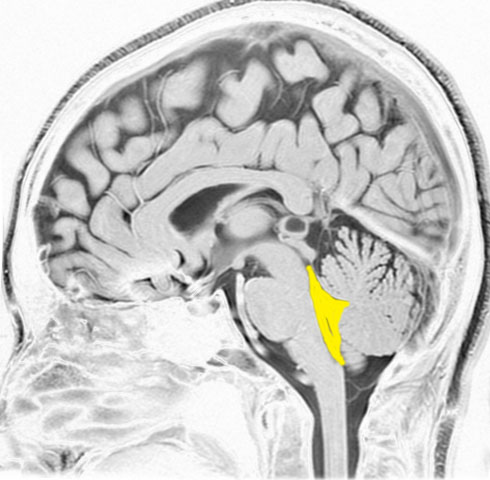

第4脳室とは

後頭部に近い所にあります。黄色が第4脳室で,髄液の通り道(出口)です。

前方には脳幹部,後ろは小脳虫部です 。

上は細い中脳水道につながって,下はマジャンディー孔と左右のルシュカ孔に開いています。